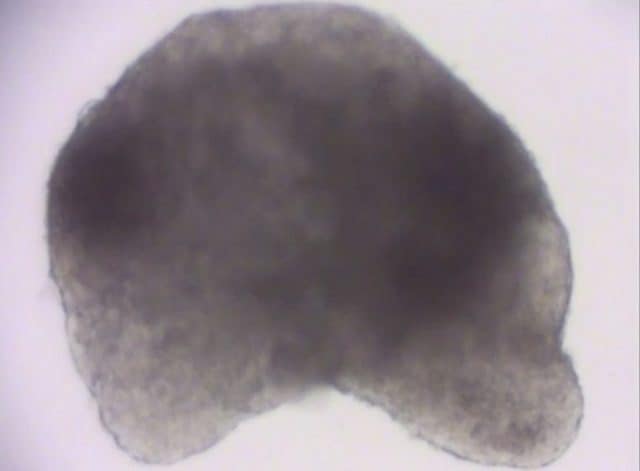

Embryon de souris développé en laboratoire. Crédit : Université de Virginie / Nature Communications

Pour la première fois dans l’histoire de Recherche les scientifiques ont créé un embryon de souris avec un cœur cette Beats complètement développé en un Boîte de Pétri (ou boîte), un « vaisseau » de laboratoire. le révolutionnaire système biologique a été réalisé à partir de cellules souches embryonnaires qui ont été savamment orchestrés par les savants ; l’embryon obtenu ne peut donner vie à une souris vivante et bien-être car plusieurs éléments fondamentaux manquent à sa « naissance », comme la partie antérieure de la cerveau, cependant, c’est l’un des résultats les plus complexes et les plus avancés dans le domaine de la recherche biologique. L’objectif des scientifiques est de permettre à la cultivation de organes humains pleinement fonctionnel dans le laboratoire, une étape qui mettrait fin aux longues listes d’attente pour greffes et cela pourrait sauver la vie de centaines de milliers de personnes.

Un organe humain tel que l’intestin, expliquent les auteurs de l’étude, est constitué de cellules qui s’organisent pour former un tube creux. Mais sans les muscles, les vaisseaux sanguins et les nerfs qui contrôlent ses fonctions, il est complètement inutile. Ainsi, la seule façon de créer des répliques d’organes humains fonctionnels est d’organiser plusieurs précurseurs cellulaires et de les entraîner à faire leur travail. Le système biologique développé par le professeur Thisse et ses collègues présente une grande variété de tissus, un cœur qui bat mais surtout une organisation ponctuelle autour du notocorde, le précurseur de la colonne vertébrale. C’est un résultat jugé « énorme ». «Ce fut un grand pas pour nous, mais cela montre que si vous avez une idée solide, elle peut être utilisée pour surmonter des obstacles et peut être développée à d’autres fins. Je dis ceci pour les étudiants : rien n’est définitif, il y a de la place pour en savoir plus et pour résoudre des problèmes », a commenté l’auteur principal de l’étude. Les détails de la recherche « Construction d’un modèle d’embryon de mammifère à partir de cellules souches organisées par un centre de signalisation morphogène » ont été publiés dans la revue scientifique faisant autorité Nature Communications.